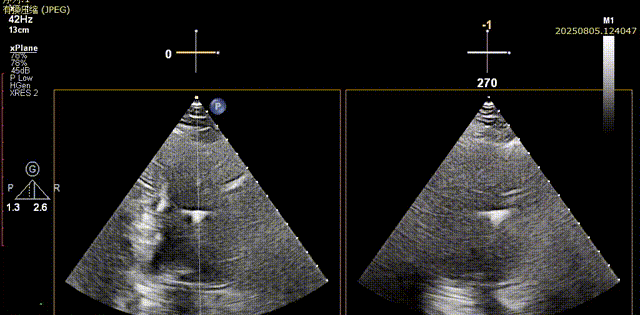

脱钩后输送器部分回收,瓣膜无位移及形变,确认瓣膜完全脱钩,回撤输送系统及导丝,超声再次评估,瓣膜位置及形态良好,无明显瓣周漏,峰值流速2.44m/s,平均压差13mmHg,患者未诉不适,入路缝合后返回病房

胸骨旁长轴评估